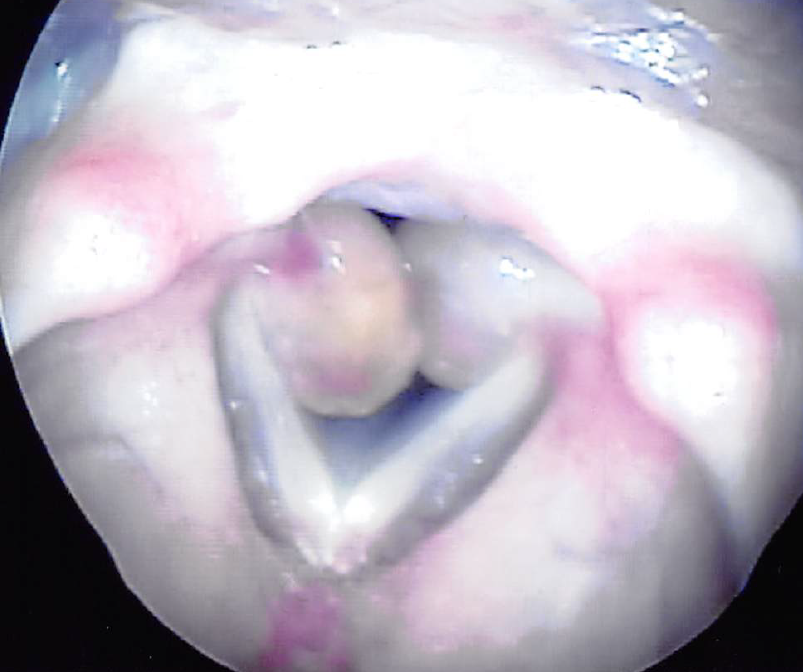

扁桃肥大とは

喉の奥にある扁桃(口蓋扁桃)が何らかの原因で肥大してしまう病気で、呼吸がしにくく、いびきや無呼吸症候群の原因にもなります。また、食事を飲み込むのに時間がかかります。治療には手術が必要な場合もあります。

喉の奥にある扁桃(口蓋扁桃)が何らかの原因で肥大してしまう病気で、呼吸がしにくく、いびきや無呼吸症候群の原因にもなります。また、食事を飲み込むのに時間がかかります。治療には手術が必要な場合もあります。